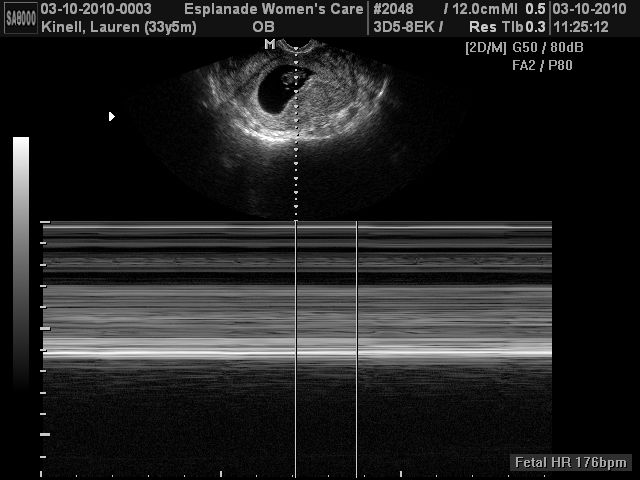

Baby Pictures!